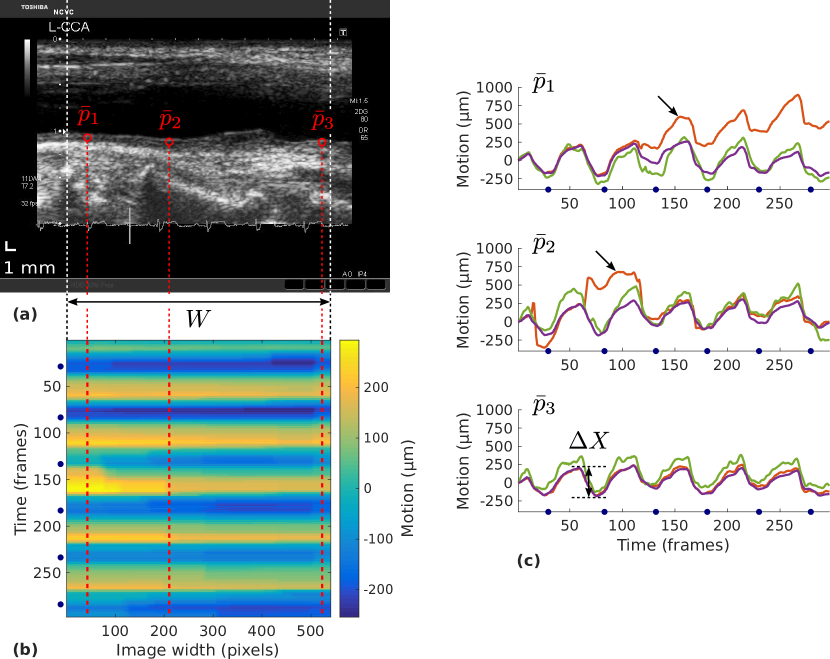

The method introduced here is devised to simultaneously extract the motion of all the points located on a line. The main steps of the method—hereafter referred to as Dynamic Block Matching (DBM)—are illustrated in Figure 2. The framework is composed of two principal operations: First, a block matching search is conducted independently for all the assessed points, then the resulting similarity maps are exploited in the context of a dynamic programming scheme to determine the global optimal displacement map of the ensemble of points. The remainder of this section is organized as follow: First the image acquisition procedure is defined, then the DBM framework is presented in detail, next the evaluation protocol is described, finally a quantitative analysis between LOKI-derived parameters and cardiovascular risk factors is proposed.

First, a ROI is determined by manually indicating the left and right borders of the full exploitable width of the far wall in order to clip out noisy regions (Figure 3a). All the subsequent steps of the framework are fully-automatic.

In preparation for a block matching scheme, the contour information is used to populate a mesh of points , with and , in the first frame of the cine-loop. One point is placed in each column of the ROI, in the center of the intima-media complex (Figure 3b,e).

In order to quantify the accuracy of the method despite the lack of ground truth, manual annotations were performed to constitute a reference. For each cine-loop, a set of three reference points , were first manually placed by an experienced analyst (GZ) in the left, center, and right part of the ROI in the first frame. These anchor points corresponded to well contrasted and distinguishable speckle patterns that remained visible through the entire duration of the cine-loop. Then, the 2D trajectories of these points were manually traced during the entire cine-loop by tracking their position in all frames of the sequence. Intra-analyst variability was also assessed for all tracked points in the testing set. Manual annotations were conducted using a graphical interface that was specifically developed for this purpose, and a Wacom Intuos Pro pen tablet for improved precision.

The DBM method was then applied to the entire ROI. The three columns specifically describing the motion of the reference points were selected for evaluation. Finally, a state-of-the-art tracking method based on Kalman Block Matching (KBM) zahnd2013evaluation was used for comparison purpose and applied to track the same set of reference points . The tracking accuracy, for both the DBM and KBM methods, was evaluated by means of a point-to-point distance comparison between the resulting estimated trajectory and the reference manual tracings.

The peak-to-peak amplitude of the motion trajectory (Figure 5c), an established LOKI-derived parameter that was demonstrated to be associated with cardiovascular risk factors zahnd2011measurement ; zahnd2012longitudinal ; tat2017reduced ; ahlgren2012longitudinal ; ahlgren2015profound ; au2016carotid , was extracted from the resulting motion field (Figure 5b,c). For each participant, was automatically determined as the average between all the local peak-to-peak amplitude values, in all the available cardiac cycles and across the entire width of the ROI.

The intra-participant variability index was introduced to evaluate the reliability of measurements based on a single point, namely to quantify LOKI reproducibility with respect to the selection of the horizontal coordinate of the initial measurement point. This parameter was assessed by means of the following procedure. For each participant, the local amplitude was automatically measured in each column of the ROI. The intra-participant variability was then established by calculating the mean absolute difference between all pairs , with , , , and the total width of the ROI.

The inhomogeneity index was introduced to quantify the consistency (or lack thereof) of the motion field across the horizontal direction of the ROI (Figure 5b). The parameter is determined as follow: A linear normalization is first applied to the motion field to scale the values between 0 and 1. The aim of this step is to generate an index that is independent of the mere amplitude of the motion. Then is obtained by calculating the average standard deviation of the normalized motion field along the horizontal direction. The purpose of this step is to detect, in any given frame of the cine-loop, the presence of spatial regions where LOKI magnitude is greater than in other regions. Such behaviour, caused by an inhomogeneous motion field, is thus reflected by a large value.

The motion was successfully extracted from all the analyzed cine-loops. The quantitative evaluation of the proposed DBM framework, showing the mean absolute () difference between the trajectories resulting from the manual reference annotations and those resulting from the method, is presented in Table 3, together with the comparison against the previously introduced KBM method. Overall, the temporal trajectories resulting from the DBM method demonstrated a good similarity with the manual reference annotations, as displayed in Figure 5c. It was also observed that the DBM method performed quite robustly, as opposed to the KBM method, which in some cases failed to capture the exact tissue motion due to progressive drift or sudden jumps to another target point. This is reflected by the Figure 6, where outliers are more numerous in the case of the KBM method.

The very nature of the DBM framework enabled for the extraction of a dense motion field . Several dynamic patterns, corresponding to different participants, are displayed in Figure 7. Although a quantitative analysis of the tracking accuracy was only performed in three local points per cine-loop, as described above, a qualitative assessment of the motion homogeneity can be obtained from these 2D fields.